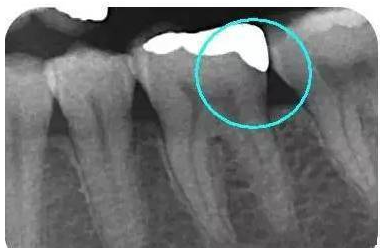

从下面这张X线中可以看出,嵌体远中边缘没有悬突,与牙体边缘密合相接。